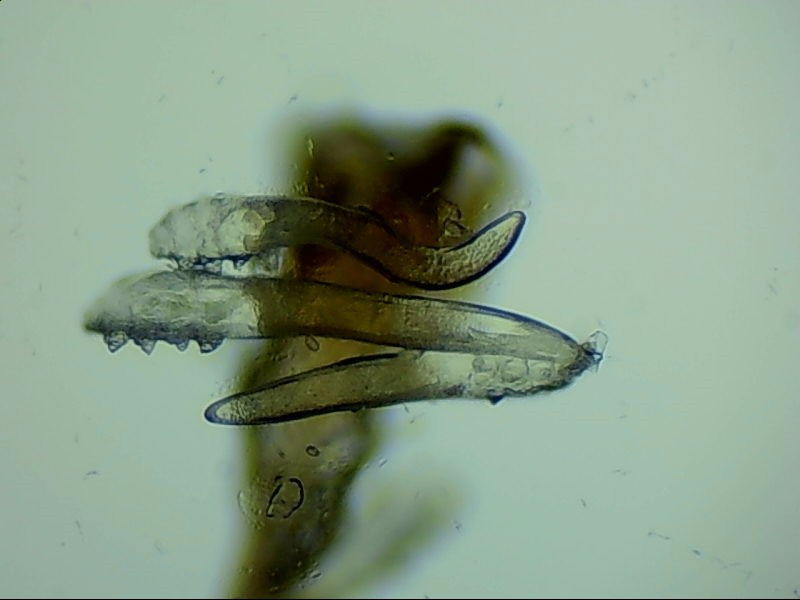

蠕形螨是螨蟲的一種,主要寄居在毛囊中。蠕形螨以分泌的油脂、分泌物為食,所以眼部寄居著蠕形螨的患者多有亂睫或睫毛脫落的癥狀。

蠕形螨寄居后,它們以睫毛毛囊里面的油脂為食。隨著油脂的缺失,睫毛會(huì)長(zhǎng)的東倒西歪,如果毛囊里的油脂都被吃光了,就會(huì)出現(xiàn)睫毛脫落這種蠕形螨性瞼緣炎的典型癥狀。

身體健康時(shí),蠕形螨就吃吃油脂,夜里爬出來(lái)活動(dòng)、交配,與我們相安無(wú)事,一旦身體的免疫力下降,蠕形螨的活動(dòng)、產(chǎn)的卵、排泄的廢物和分泌的分泌物都會(huì)引起過(guò)敏反應(yīng)?;颊邥?huì)出現(xiàn)眼癢、異物感、眼干、瞼緣充血、鱗屑、睫毛根部袖套狀分泌物及睫毛脫落等癥狀,嚴(yán)重者可并發(fā)結(jié)膜及角膜病變,給生活帶來(lái)不便和困擾。